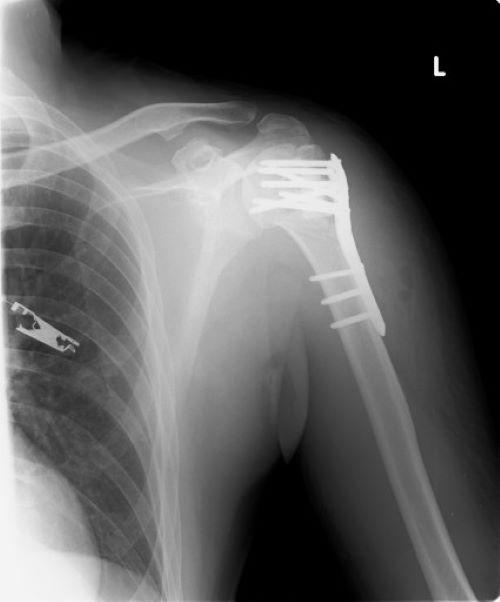

「健康な老後の大事な三つ!!」2022.4.32年前の2020年7月、コロナの第一波が収まりかけていた頃、両手に荷物を持って転倒し受け身が取れず左肩を骨折し、写真の如く手術で肩にプレートを入れました。骨折が完治したので昨年2021年10月にプレートを取り除きました。リハビリにより腕立て運動も可能に成り、腕の可動域が骨折前の8割くらい戻り、先週の岡山赤十字病院の診察で骨折の治療は終了と成りました。時に傷口がつっぱり痛みを感じますが、痛みが無くなるのは数年掛かるようです。ドクターからは「こういう治療でもう二度と病院に来ないように。」と言われました(笑)。私が最近股関節の軟骨が減り、痛くて走る事を止めてエアバイクを漕いでいると言うと、「高齢者に成り歩く事が減ると筋力が落ち、歩けなくなる。エアバイクかプールで歩き、腿の筋肉を維持する事。塩・砂糖の接種を控える事。睡眠を充分とる事。以上に気を付けて寝たきり成らないよう健康に過ごしてください。」と言われました。